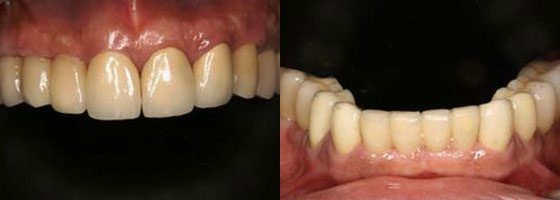

經過一年多牙周病治療與人工植牙重建病患恢復了完整的牙齒。